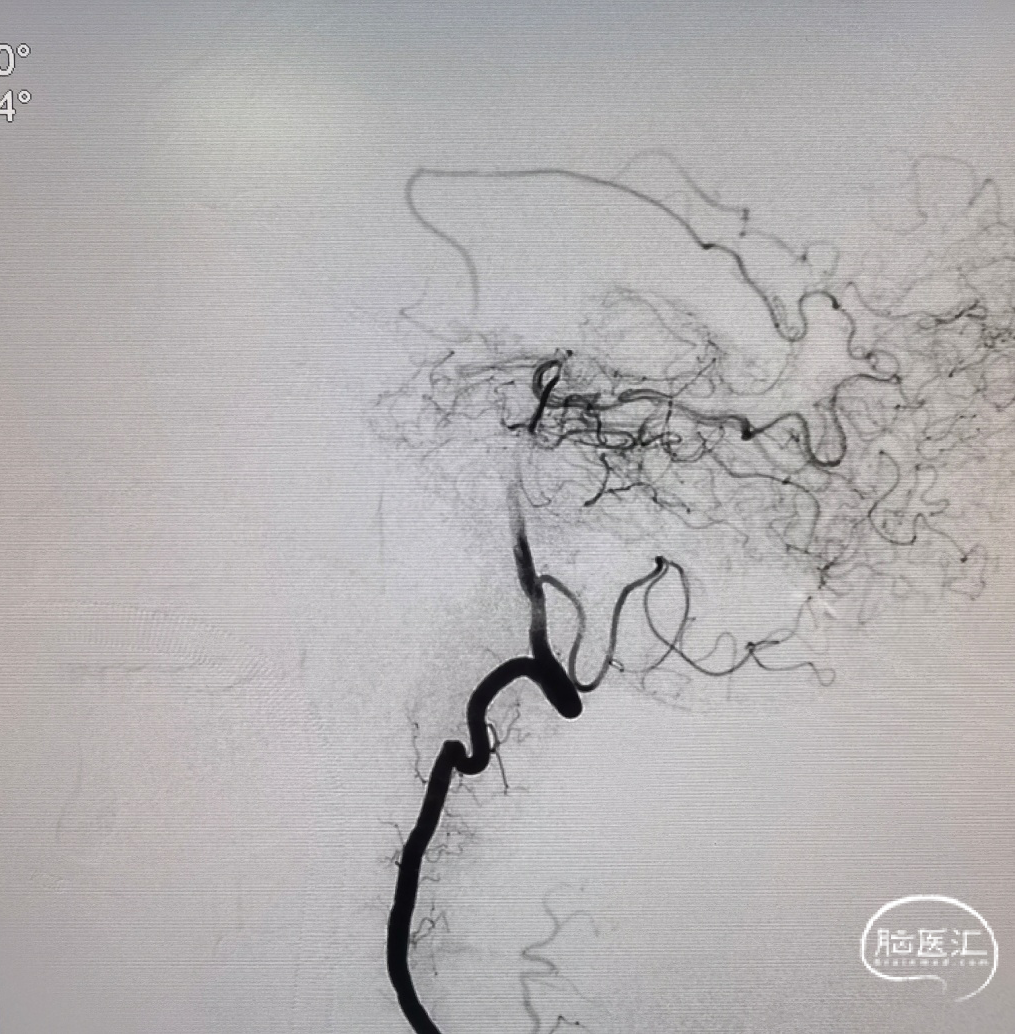

术后正侧位造影:全程血流恢复满意。